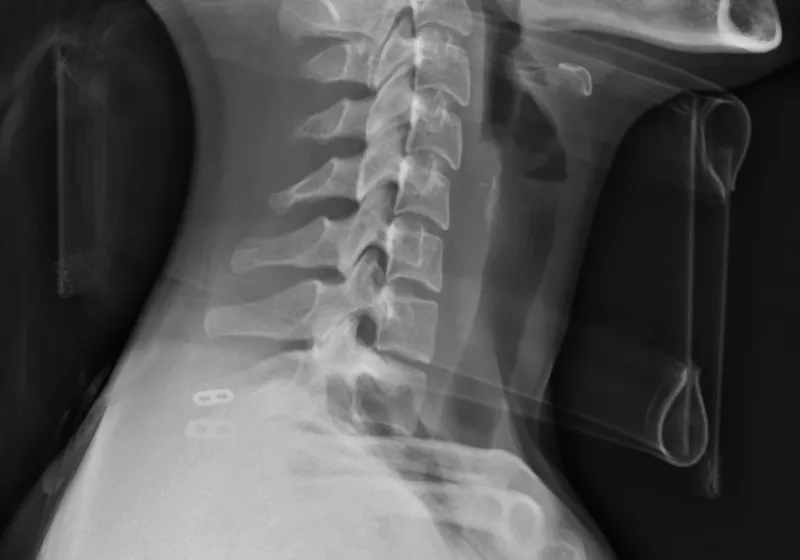

Researchers at Keio University have begun using induced pluripotent stem cells (iPS) to treat and maybe even cure severe spinal cord injuries. The iPS technology was first conceived by Shinya Yamanaka in 2006, who later received the Nobel Prize with John Gurdon for discovering that they could reprogram adult cells…